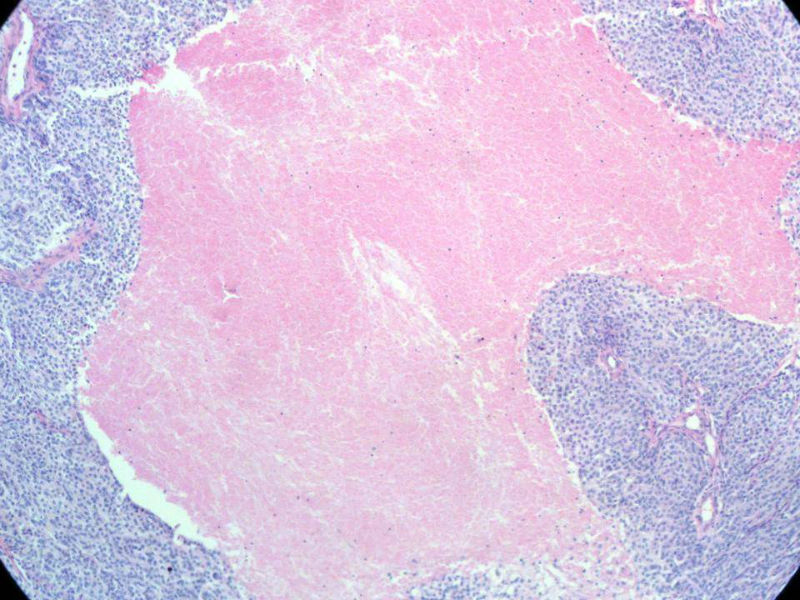

肿瘤性坏死本身是凝固性的一种类型,特点是细胞坏死,但组织轮廓仍存在。其坏死组织是肿瘤成分。

普通的凝固性坏死一般是由血栓栓塞引起的,梗死灶与周围正常组织之间都有炎性充血带。

这是我们科室最近遇到的一例肿瘤,所发生的肿瘤性坏死。

描述:脾梗死